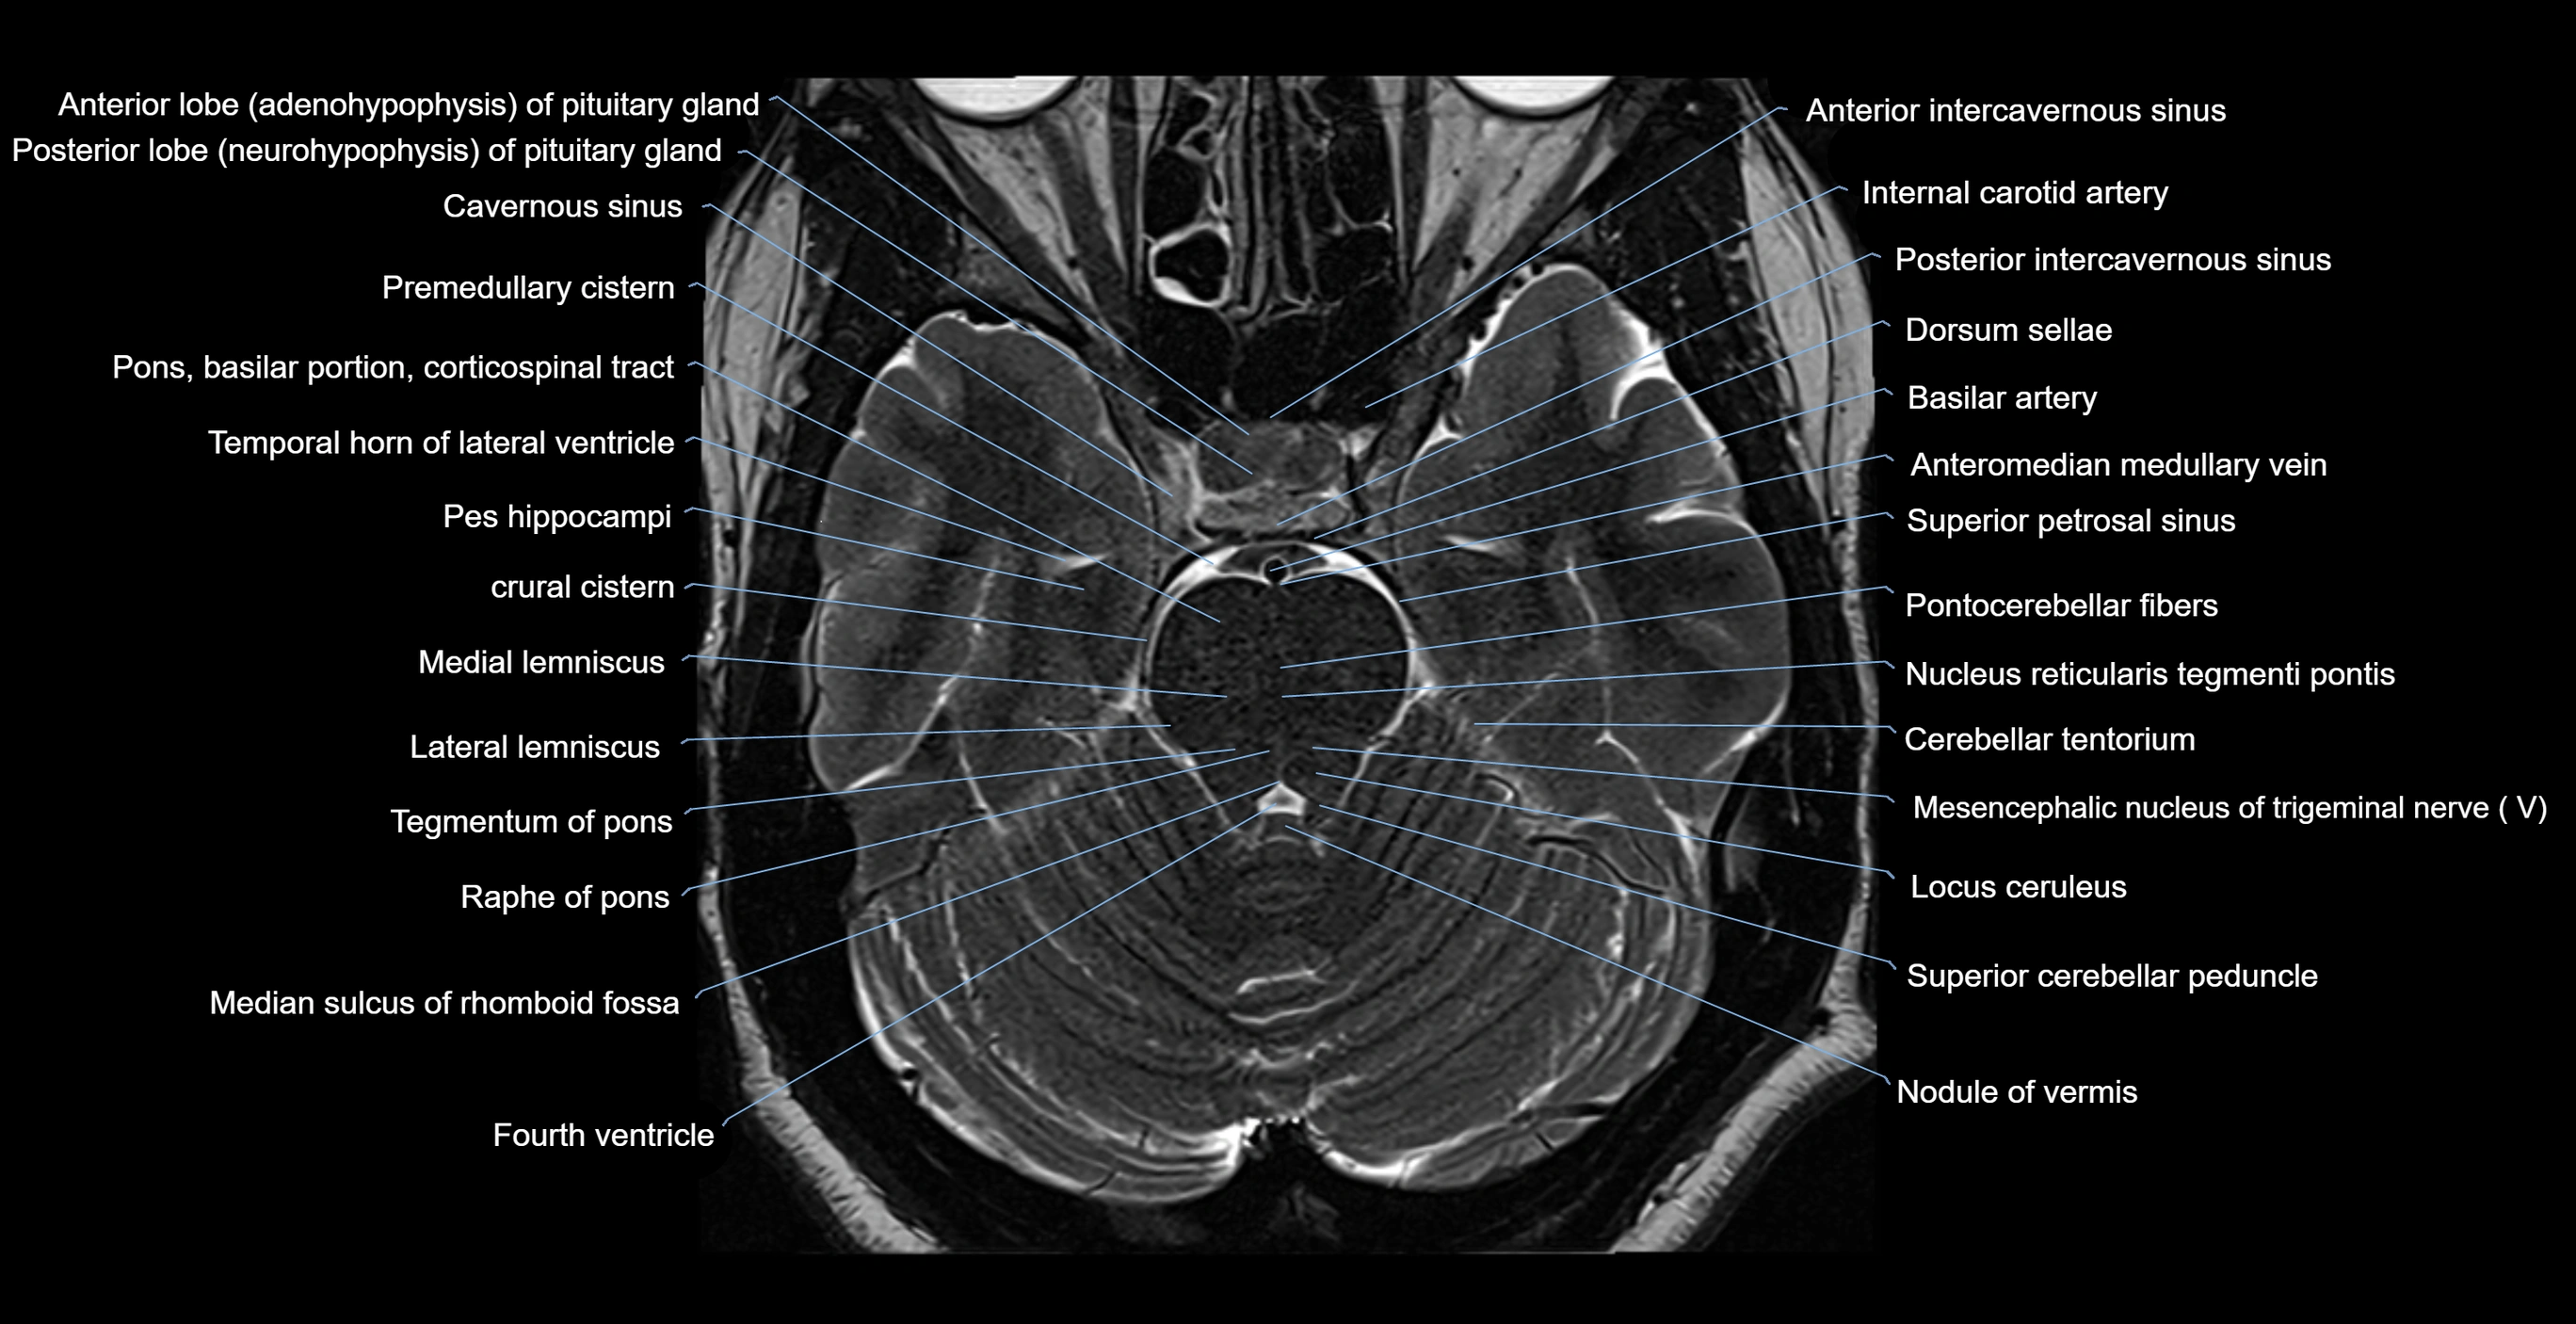

MRI images